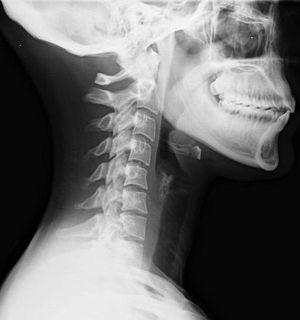

Lateral neck X-ray of whiplash.jpg

Lateral view X-ray of whiplash showing a loss of normal lordosis of the cervical spine